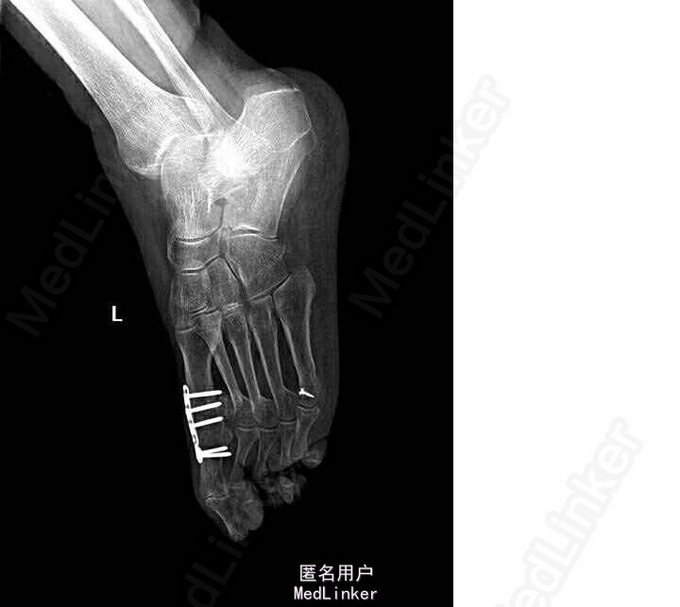

64岁,女性。3年前发现因双侧扁平足,双踇趾外翻,左侧较重,于我院行左足截骨矫形内固定术。1年前感左足踇趾疼痛,诊断为周围神经炎,予以弥可保治疗后感症状缓解。1月后仍感左足踇趾疼痛,行走时加重。

查体:双足呈扁平畸形,负重位足面间距增宽。左踇趾呈锤状趾畸形,活动度差,踇趾外侧有一约5cm手术瘢痕,左足踇趾根部内侧皮肤增厚粗糙,颜色发红,皮肤无破溃。左足底及第5趾外侧可见胼胝增厚。 X光片示扁平足术后改变

诊断:双侧扁平足(左侧重),左足截骨矫形术后,左足第一、五跖趾骨关节炎 局麻下行“左足矫形术(第五趾间关节融合内固定,第一、三、五趾骨屈肌腱松解,第一趾骨伸肌腱紧缩术)”。